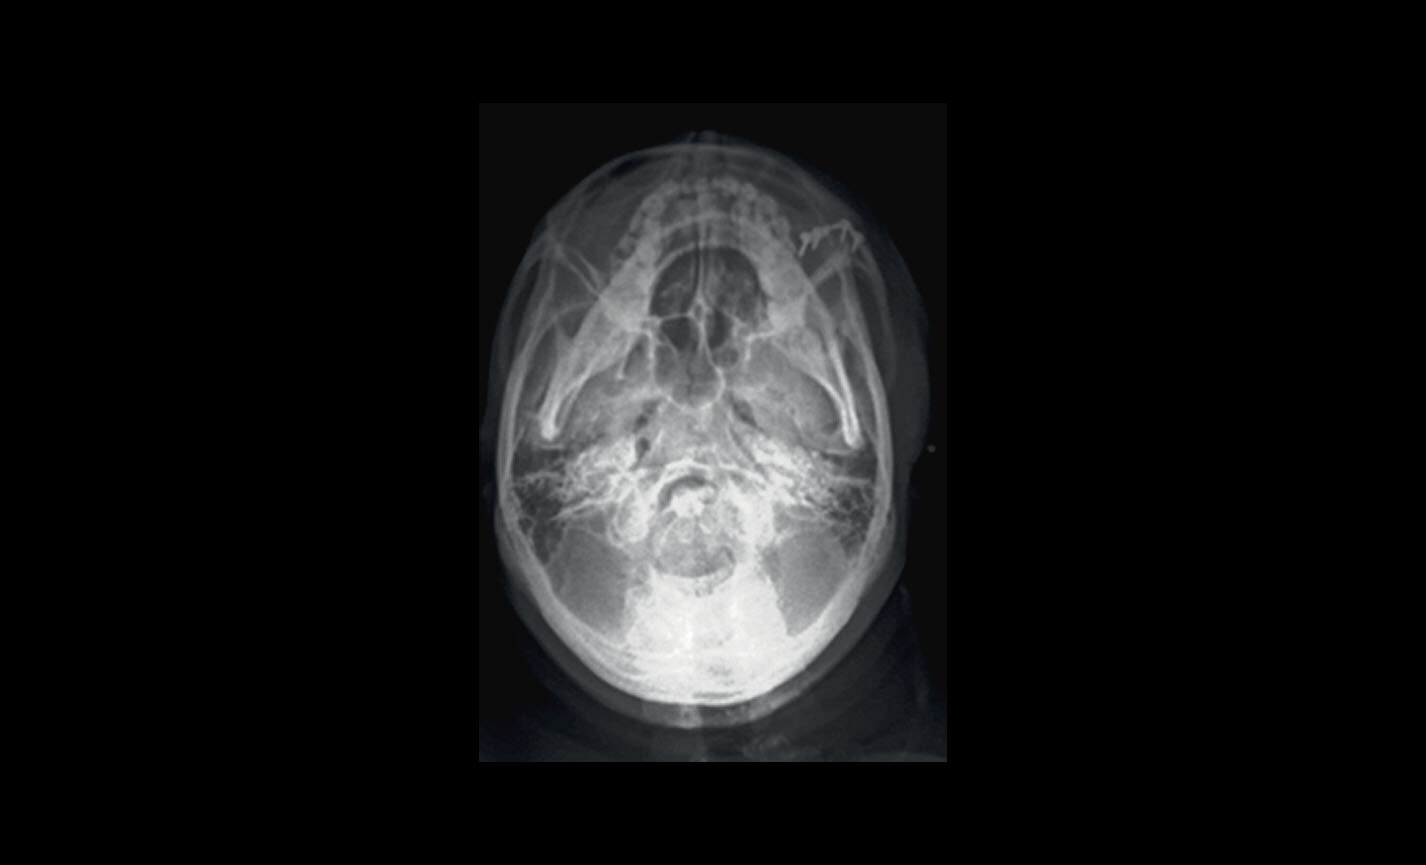

Projections menton-vertex, y compris les incidences de Waters et de Towne renversées

Téléradiographie

Latéro-latérale : avec détails des os et des tissus mous en évidence, fondamental pour les études céphalométriques.

Téléradiographie

Antéro-postérieure : pour investiguer les asymétries et les malocclusions en vue d’un traitement correct.